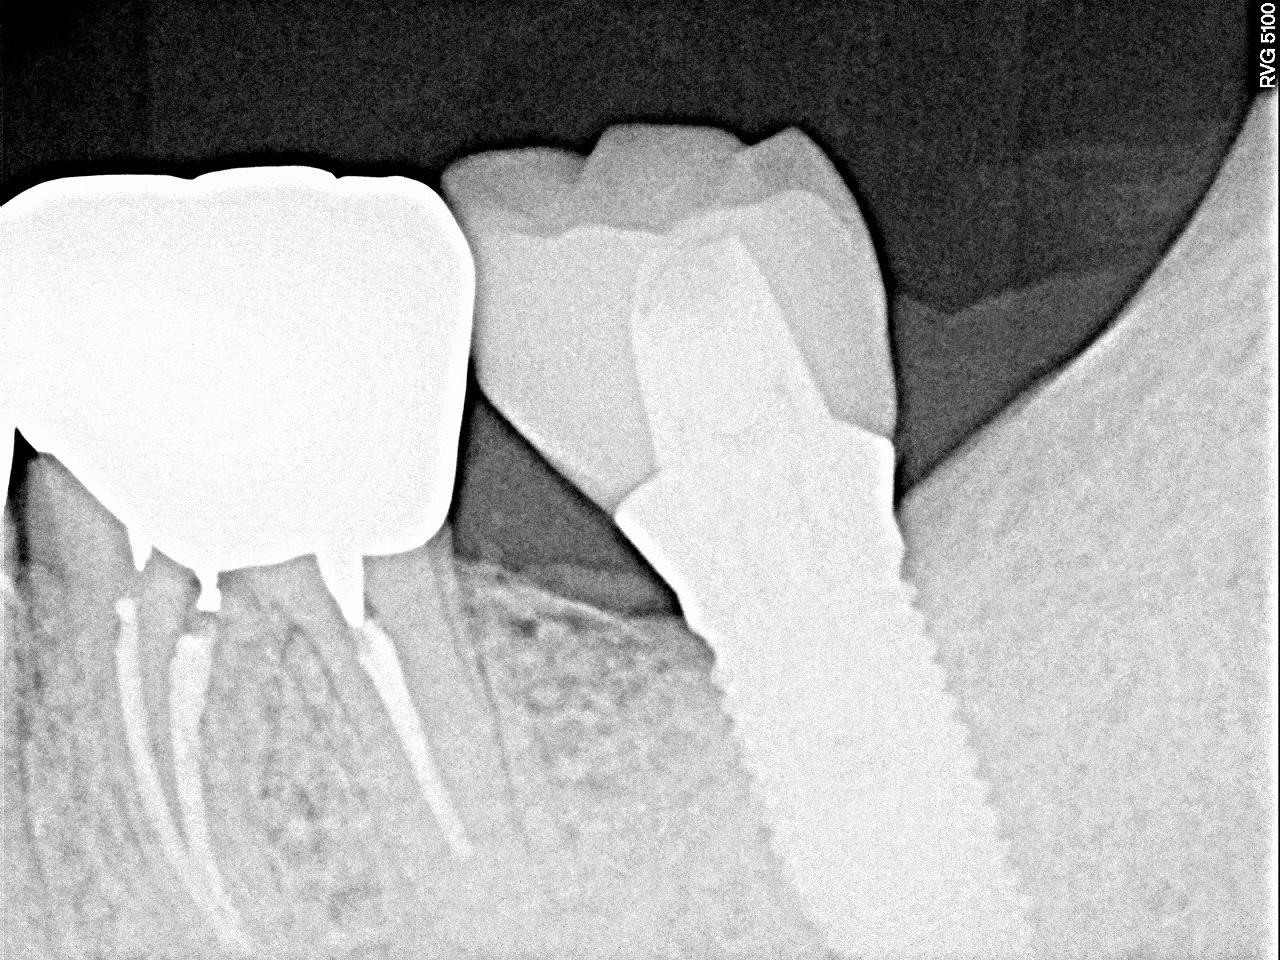

術後のレントゲン、CTになります。| |広島市安佐南区の歯科医院 術後のレントゲン、CTになります。 トップ お知らせ・ブログ 術後のレントゲン、CTになります。 術後のレントゲン、CTになります。 Web診療予約 初めての方へ 選ばれ続ける理由 院内設備について 歯が痛いしみる一般歯科 歯がぐらぐらする歯周病 健康な歯を保ちたい予防歯科 子供の虫歯予防をしたい小児歯科 銀歯をセラミックに審美歯科 白い歯を目指しませんか?ホワイトニング 矯正専門医がいるので安心矯正歯科 抜けた歯を補いたいインプラント・入れ歯 医院案内 スタッフ紹介 メリィハウス歯科クリニックオフィシャルホームページ ラベンダー歯科クリニックオフィシャルホームページ お知らせ・ブログ ホーム 診療科目 一般歯科 歯周病治療 予防治療 小児歯科 審美治療 ホワイトニング 矯正歯科 入れ歯・インプラント マウスピース矯正 初めての方へ 院長・スタッフ 設備紹介 医院案内・アクセス メニューを閉じる